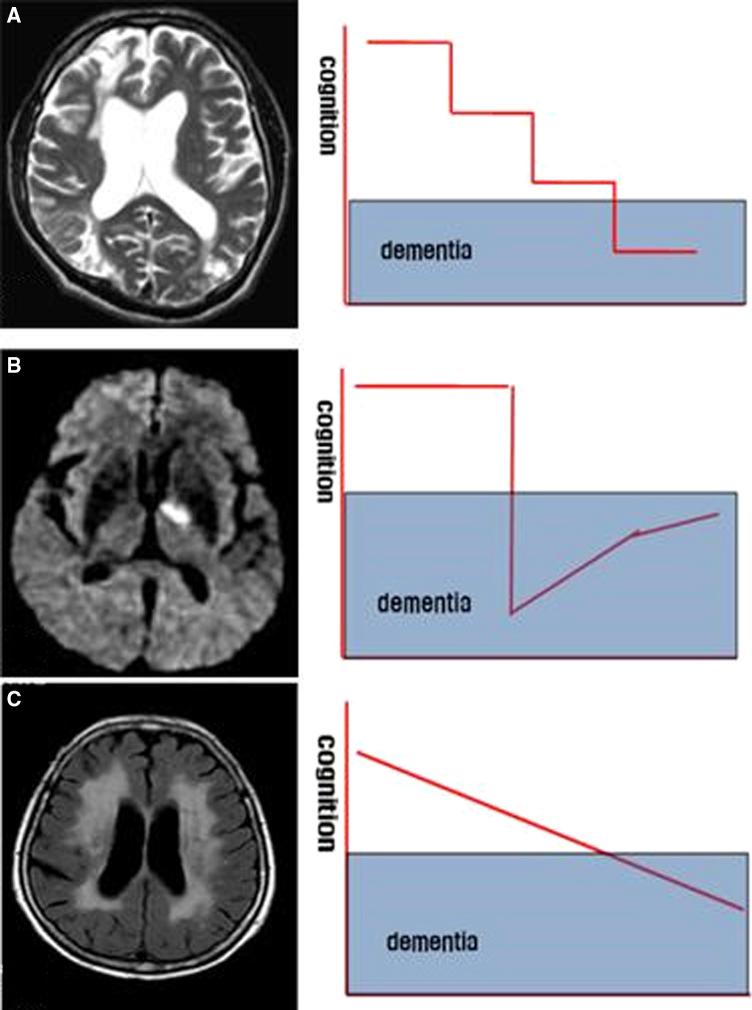

White matter hyperintensities (WMHs) are frequently seen on brain magnetic resonance imaging scans of older people. Usually interpreted clinically as a surrogate for cerebral small vessel disease, WMHs are associated with increased likelihood of cognitive impairment and dementia (including Alzheimer's disease [AD]). WMHs are also seen in cognitively healthy people. In this collaboration of academic, clinical, and pharmaceutical industry perspectives, we identify outstanding questions about WMHs and their relation to cognition, dementia, and AD. What molecular and cellular changes underlie WMHs? What are the neuropathological correlates of WMHs? To what extent are demyelination and inflammation present? Is it helpful to subdivide into periventricular and subcortical WMHs? What do WMHs signify in people diagnosed with AD? What are the risk factors for developing WMHs? What preventive and therapeutic strategies target WMHs? Answering these questions will improve prevention and treatment of WMHs and dementia.